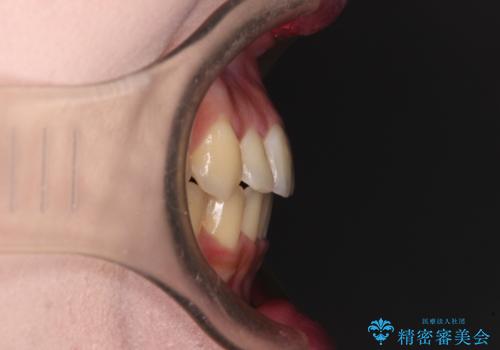

- 前歯のデコボコを気にして来院された患者様です。

上顎右側犬歯が八重歯になっており、それによって奥歯が前方に移動しているため、右側の咬み合わせの改善が必要と判断されました。